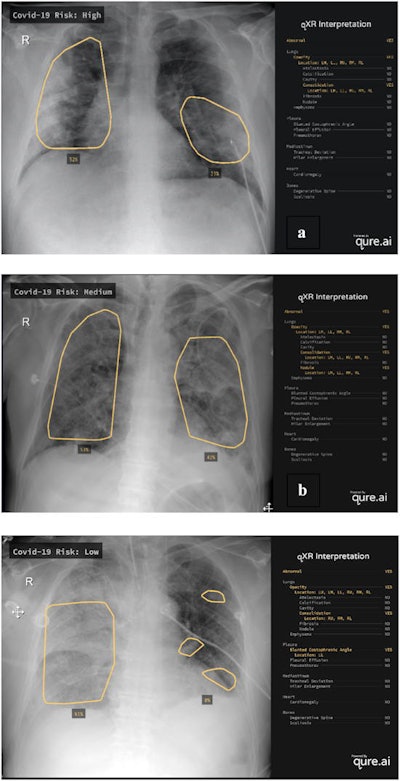

After receiving additional training on COVID-19 patients, the modified algorithm -- called M-qXR -- produces a risk score that stratifies patients into no-risk, low-risk, medium-risk, or high-risk categories for COVID-19 based on the presence of pulmonary opacities and consolidations with a bilateral and peripheral distribution, according to the researchers. The institution used the software to help stratify at-risk patients to receive further testing.

Examples of chest radiographs evaluated by the M-qXR algorithm. M-qXR assigned a high (a), medium (b), and low (c) COVID-19 risk score based on the presence of radiographic abnormalities on the chest radiographs presented. Images and caption courtesy of D. Hipolito Canario et al and Intelligence-Based Medicine through Creative Commons Attribution 4.0 International License.In the first part of the study, the researchers compared the performance of the algorithm with a majority consensus interpretation by four radiologists with an average of 22 years of experience. Each of the radiologists independently read the 625 chest x-rays over the eight-week study period.

Overall, the algorithm agreed with 98% of the radiologist interpretations and yielded strong results for identifying pulmonary opacities and the presence or absence of pulmonary consolidation.